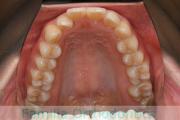

- ≫治療前

上顎

下顎

- ≫治療後

全体的なでこぼこを治したいということで来院されました。上顎は右は4,左と下顎両側は5番を抜歯して、マルチブラケット法にて治療を行いました。2年強、25回程度の通院をしていただきました。

非常に強いでこぼこですので、後戻りのリスクは高めであると思われます。